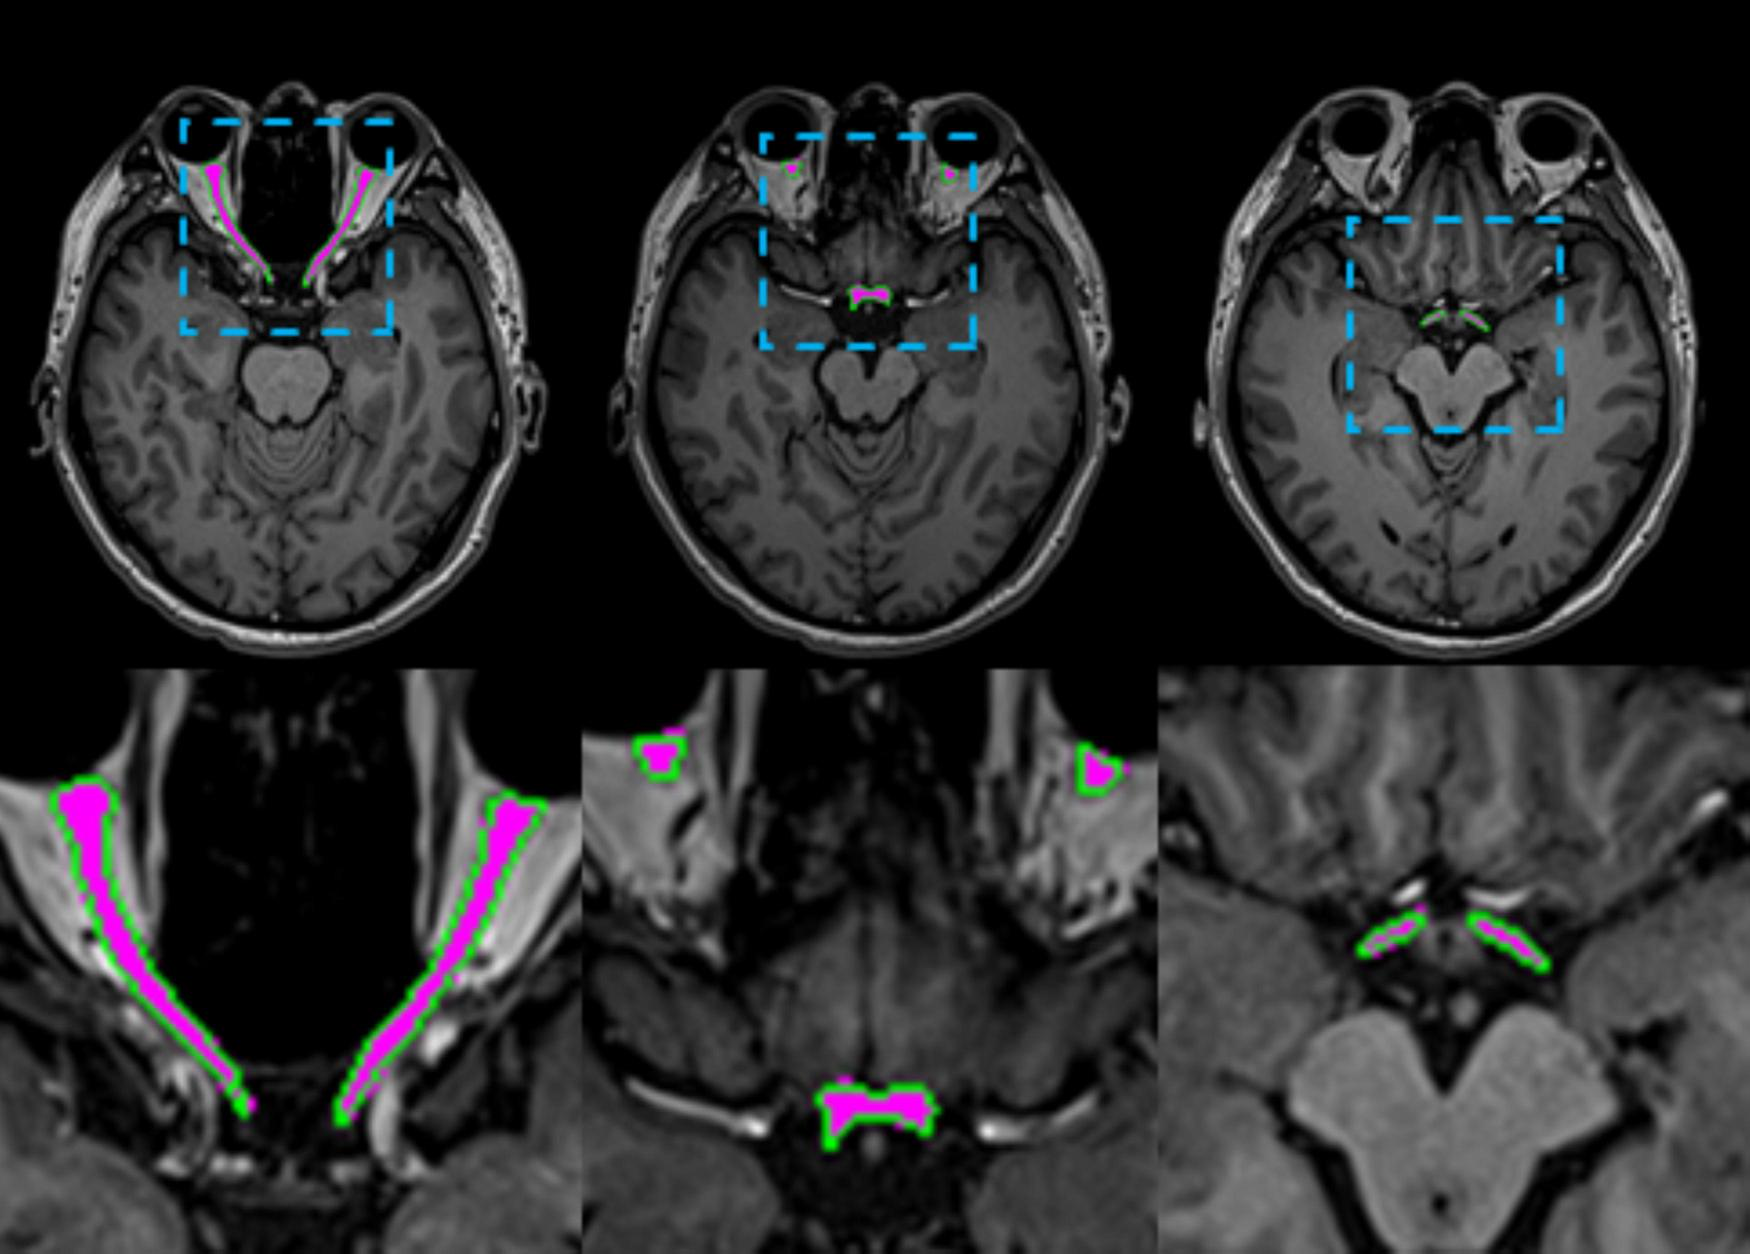

FIGURE 5

Visual comparisons of AVP segmentation examples are shown. The predicted AVP contours are overlaid in green on a representative axial T1-weighted MRI of the brain from one test subject, with manual annotations overlaid in magenta for reference. The inset provides a close-up comparison of the predicted values.

The 3D UX-Net model exhibited minimal volumetric discrepancy in AVP predictions (1514.56 ± 165.52 mm3) compared to ground truth annotations, with detailed per-subject performance metrics documented in Table 3. As illustrated in Figure 5, automated contours generated by 3D UX-Net showed high anatomical concordance with manual delineations, achieving submillimeter boundary accuracy (0.23 mm) that meets precision requirements for image-guided surgical interventions.